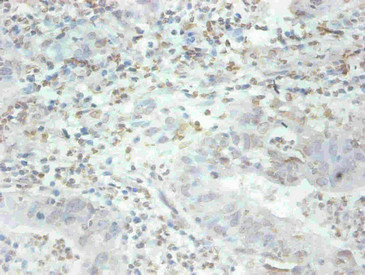

圖片:

產品描述:MFGE8單克隆抗體(CUSABIO貨號:CSB-MA079741A0m)是針對乳脂肪球EGF因子8蛋白研發的科研專用試劑,該靶標蛋白在細胞粘附、信號傳導及免疫調節中發揮重要作用,尤其參與脂質代謝相關通路和細胞間相互作用機制研究。本產品采用高特異性單克隆抗體技術,經嚴格驗證可識別人源MFGE8抗原表位,適用于酶聯免疫吸附測定(ELISA)進行蛋白質定量分析,以及免疫組化(IHC)實驗用于組織定位研究。其核心優勢包括精準的抗原結合能力與穩定的批次一致性,能夠滿足細胞生物學、腫瘤微環境、代謝疾病等領域的科研需求,特別適用于乳腺組織、免疫細胞及相關病理模型的分子機制探索。該抗體為凍干粉劑型,建議用戶根據實驗體系優化使用方案,通過靶向MFGE8蛋白的功能解析,助力細胞信號網絡、組織修復機制等前沿課題研究。

應用范圍:ELISA,IHC

Application Recommended Dilution IHC 1:50-1:500 -